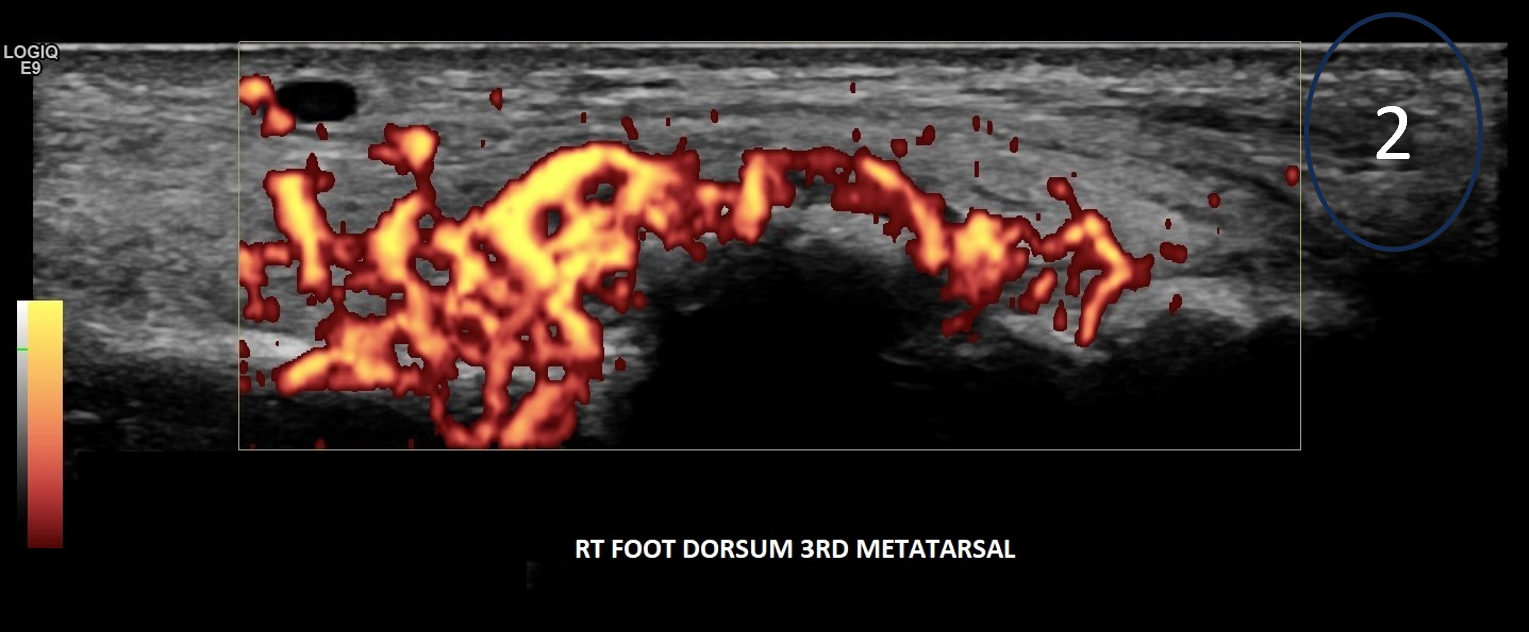

A 29-year-old female, presented with pain and a lump on the dorsum of her right foot. She was training for a 10km run and had been struggling with running over a 6-week period. No history of trauma or erythema to the skin. The clinical suspicion was a ganglion, and the patient was referred for an ultrasound scan for further assessment.

On the dorsum of the foot, ultrasound demonstrated marked cortical irregularity and callus formation around the third metatarsal shaft accounting for the palpable ‘lump’ with surrounding soft tissue swelling (Figure 1). On power Doppler, there was marked peripheral vascularity in the surrounding soft tissues (Figure 2). Incidentally, there was also cortical irregularity and callus formation around the second metatarsal shaft although the patient was not particularly tender here whilst scanning (Figure 3). The cortical irregularity in the second metatarsal shaft was minimal when compared to the third metatarsal and there was no neovascularisation on power Doppler indicating this was an older/mature injury.

Ultrasound appearances in keeping with acute and chronic stress fractures. A radiograph confirmed old and new callus formation (Figure 4). Conservative treatment comprised rest and analgesia. Surgery is generally reserved for stress fractures that do not heal.